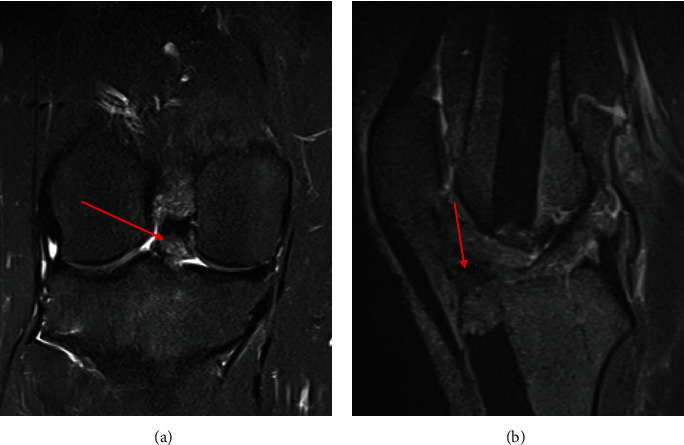

异位骨化是软组织内的异位片状骨形成,可导致严重的功能限制。异位骨化有多种潜在病因,包括肌肉骨骼创伤和创伤性脑损伤。膝关节内 HO 比较罕见,通常位于十字韧带内。我们报告了一例 24 岁女性的病例,她在一次车祸中多处下肢骨折,两年半后出现右膝关节疼痛加重和膝关节伸展受限。体格检查显示膝关节前部疼痛、伸展受限,并可触及髌下突出。影像学检查显示髌骨后肌腱、胫骨前平台近端关节内骨赘。使用70°关节镜进行诊断性关节镜检查,发现胫骨前平台近端有HO,在直视下使用高速毛刺将其切除。在三个月的随访中,患者仍无症状,并恢复了运动。髌后肌腱、关节内膝关节前HO是一种罕见的临床病症,但可以在70°关节镜直视下成功安全地进行切除。

Heterotopic ossification is ectopic lamellar bone formation within soft tissue and can result in significant functional limitations. There are multiple underlying etiologies of HO including musculoskeletal trauma and traumatic brain injury. Intra-articular HO of the knee is rare and is typically located within the cruciate ligaments. We report a case of a 24-year-old female who presented with worsening right knee pain and limited knee extension two and a half years after a motor vehicle crash with multiple lower extremity fractures. Physical examination of the knee revealed anterior pain, limited extension, and a palpable infrapatellar prominence. Imaging showed a retropatellar tendon, intra-articular excrescence of bone proximal to the anterior tibial plateau. Diagnostic arthroscopy with a 70° arthroscope identified HO at the proximal anterior tibial plateau, which was excised with a high-speed burr under direct visualization. At the three-month follow-up, the patient remained asymptomatic and returned to sport. Retropatellar tendon, intra-articular anterior knee HO is a rare but debilitating clinical entity that can be successfully and safely managed with excision under direct visualization using a 70° arthroscope.